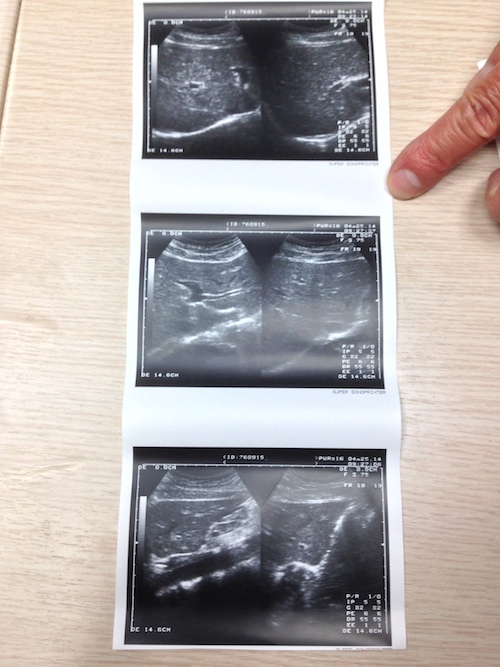

無論怎麼看⋯⋯都像孕婦的超音波檢查呀~我拿給朋友看,還以為我把女友⋯⋯

超音波給我的感覺是冰冰涼涼,所長拿著一根有滾輪的棒子,塗上特殊液體,然後在我肚子和脖子滾動,一旁的小螢幕有黑白畫面在動,就像電影裡和肥皂劇裡的情節那樣⋯⋯

所長跟我說看超音波幾個要點,

- 黑色的點

- 白色的點

- 陰影

是問題所在喲~幸運地我安然無恙:D~

拿這些影像去給親朋好友看,大多都會嚇一跳,甚至開玩笑說你要生了⋯⋯

由於沒有印給我的份,所以就用手機拍下來囉~